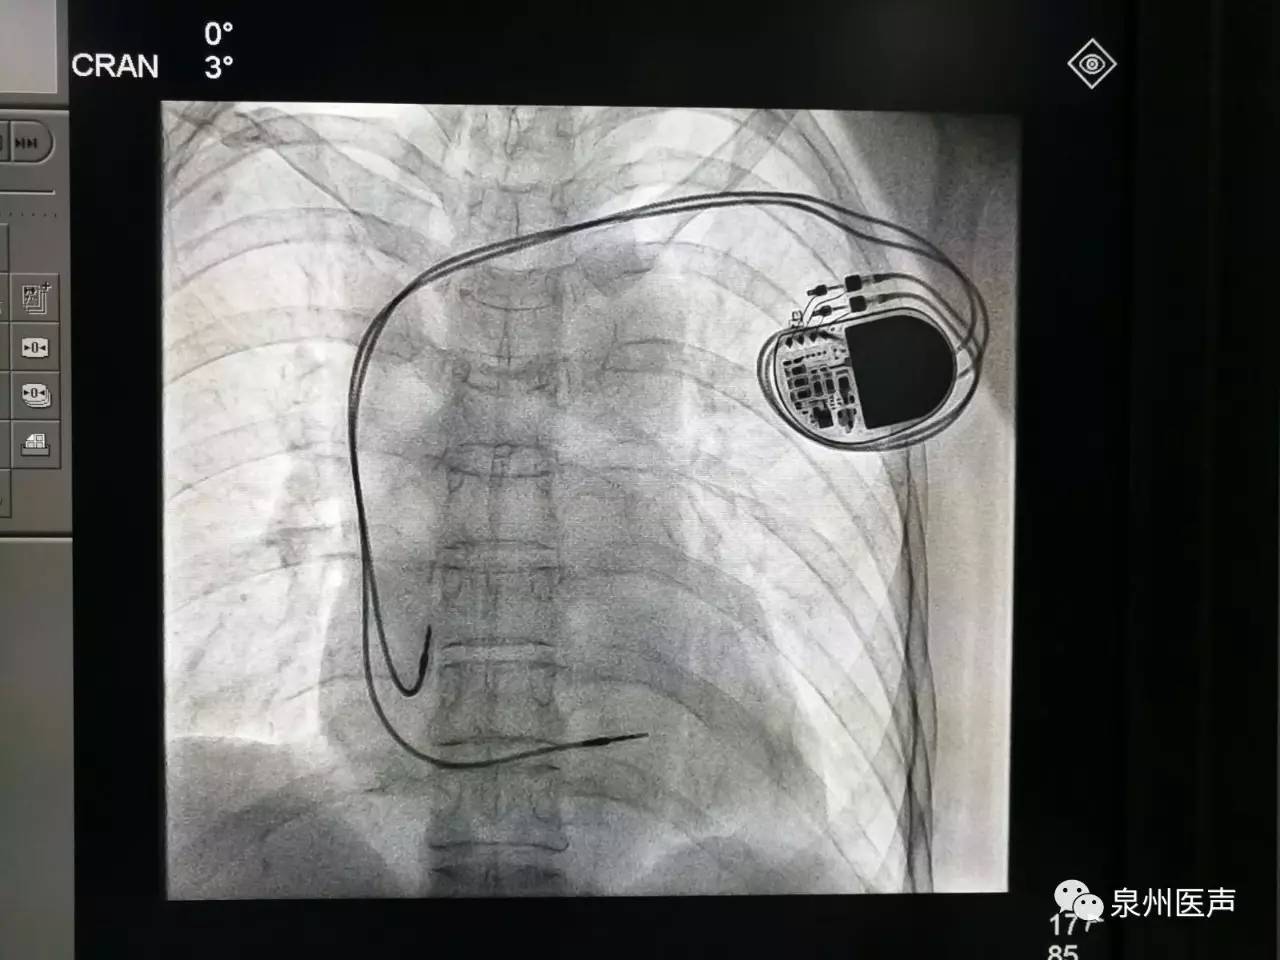

利用心跳為心臟植入物供電!

大開眼界!

起搏器 2019-02-15

心臟起搏器的日常護理

心臟起搏器出院的宣教,是心內科醫(yī)護人員不容忽視的一項工作

行業(yè)數(shù)據(jù) 2019-02-13